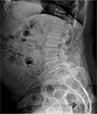

Patient Cases After picAfter

• Patient Reviews before image case 2After Surgery